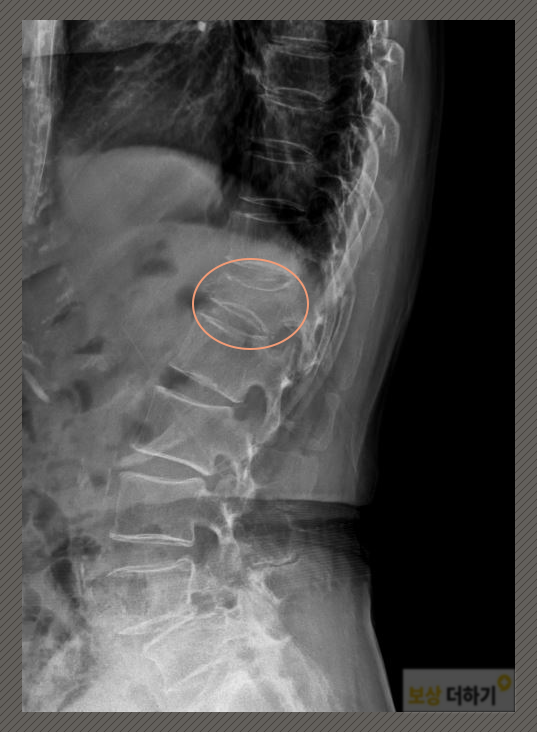

화장실 미끄러짐 - 흉추 골절 - K 님은 자택 화장실에서 넘어지는 사고를 겪으셨어요. 그 후 허리 쪽에 통증이 느껴져 내원을 하셨습니다. 검사 결과는 S22070 흉추 11 및 12 부위의 골절 진단을 받으셨어요. 이곳은 등뼈에 해당되는데요. 허리 뼈와 연결되는 곳이어서 허리 쪽에 불편함을 느끼셨던 것이죠.

위의 사진에서 흉추 12번 척추뼈가 찌그러진 모습을 볼 수 있습니다. 다른 뼈들과 다르게, 넘어지면서 충격을 받아 위아래로 눌려있습니다. 따라서 '압박골절'이라고 하는데요. 이것을 완전히 펴서 원래의 형태로 돌아오게 할 수 없다는 것이 문제입니다. 즉 한번 압박골절된 척추뼈는 영구적인 장해가 남는 것입니다.